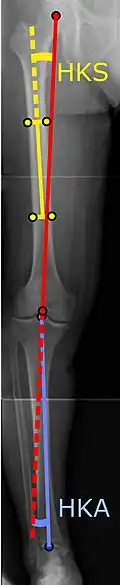

To indicate knee replacement in case of osteoarthritis, its radiographic classification and severity of symptoms both should be substantial. Such radiography should consist of weightbearing X-rays of both knees: AP, lateral, and 30 degrees of flexion. AP and lateral views may not show joint space narrowing, but the 30-degree flexion view is most sensitive for narrowing. Full-length projections also are used in order to adjust the prosthesis to provide a neutral angle for the distal lower extremity. Two angles used for this purpose are:

- Hip-knee-shaft angle (HKS),[10] an angle formed between a line through the longitudinal axis of the femoral shaft and its mechanical axis, which is a line from the center of the femoral head to the intercondylar notch of the distal femur.[12]

- Hip-knee-ankle angle (HKA),[11] which is an angle between the femoral mechanical axis and the center of the ankle joint.[12] It is normally between 1.0° and 1.5° of varus in adults.[13]